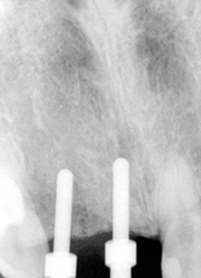

A 43 year-old lady has lost #7 and 8 due to caries for ~ 2 year. It appears that the ridge is wide (Fig.1). To place implants in ideal position, cone beam CT is planned. Models are mounted (Fig.2); diagnostic wax-up is finished (Fig.3). Drill sleeves (arrowheads in Fig.4; 10 mm long, 2.2 mm in diameter; Straumann) are placed lingual to the incisal (I) edges of the neighboring teeth. The position of drill sleeves is confirmed by CT: between the incisal edge and the cingulum (Fig.5). The cross sections at #7, 8 and 9 are shown in Fig. 6, 7 and 8, respectively. However, the long axis of the sleeve (S) or the natural tooth #9 is not aligned with that of the alveolar ridge. This orientation is good from prosthetic viewpoint, but we cannot place a long or wide implant. The lateral view of the three-dimensional image shows that the long axis of the crown (C) of #9 is not in line with that of its root/ridge (R, Fig.9). It appears that the trajectory of an implant should be not decided by wax-up, but should be adjusted to accommodate the morphology of the alveolar ridge. In all, the drill sleeve (S) should be moved and tilted more labially to place the longest and largest implant.